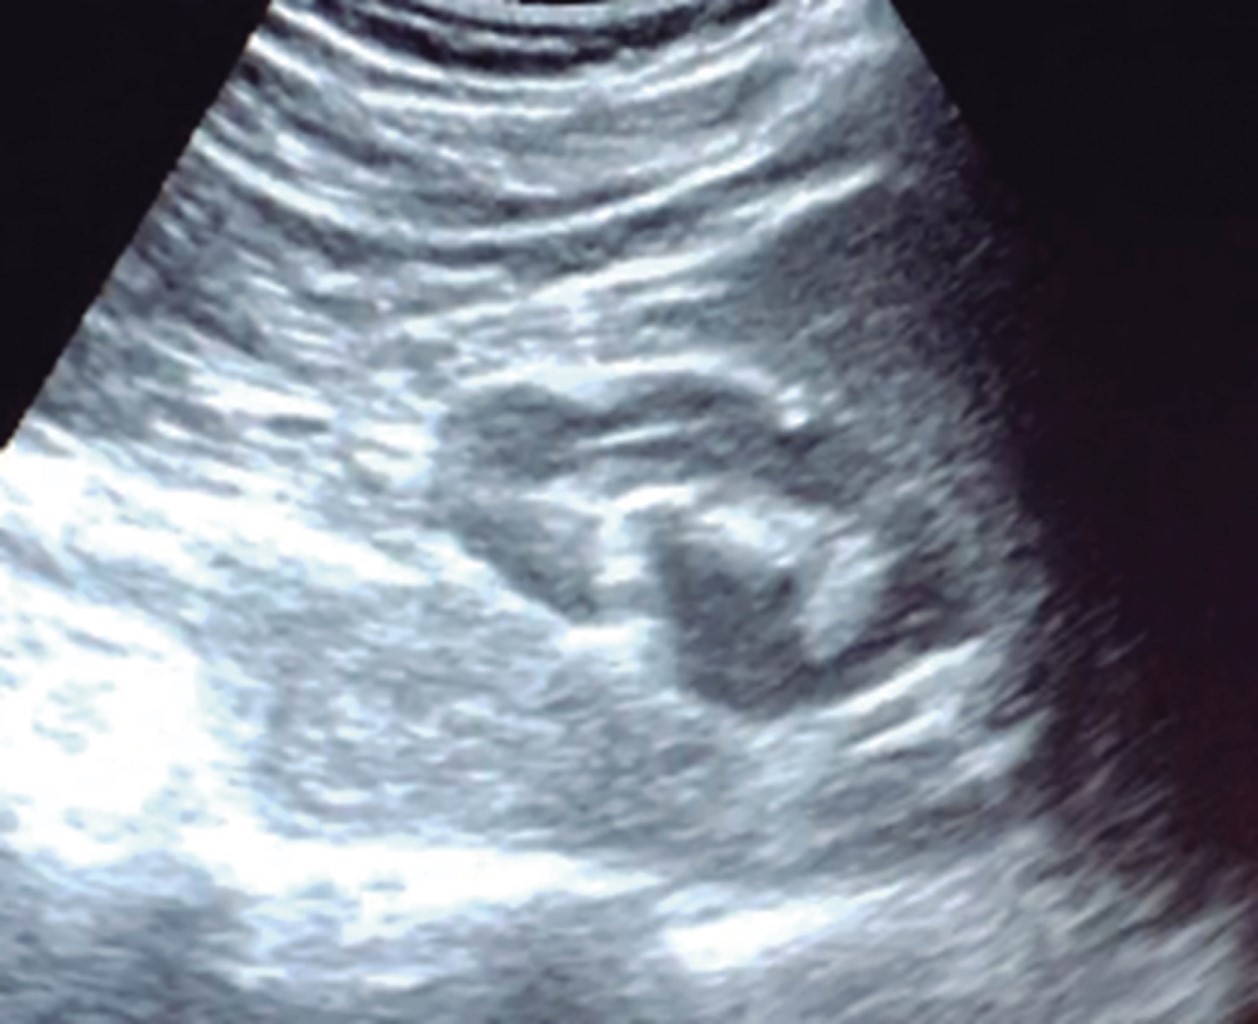

El cirujano general aborda particularmente problemas clínicos que incluyen el aparato digestivo, el cuello, la pared abdominal y los trastornos del sistema circulatorio y el tórax. Un artículo publicado en 2008, por Lindelius,15 demostró que la implementación del ultrasonido por parte del cirujano general en casos de dolor abdominal agudo incrementó en 7.9% la precisión diagnóstica. En la consulta cotidiana de la especialidad, incorporar el rastreo sonográfico al área explorada agrega minutos al examen clínico que aportan datos de notable valor por la objetividad y precisión. El abdomen suele ser el sitio que los cirujanos generales exploramos con más frecuencia. Es posible en una consulta cotidiana hacer todo el protocolo de ultrasonido de abdomen superior en minutos, que incluye ambos cuadrantes superiores y los flancos, pudiendo observar el hígado, la vesícula y los conductos biliares, ambos riñones, el bazo, parte del páncreas y, con ayuda del Doppler color, los principales vasos de la región como la vena cava inferior, la aorta abdominal, la vena porta, los vasos esplénicos y la arteria hepática. Puede haber limitantes como el contenido gástrico, el nivel de llenado de la vesícula biliar o la constitución del paciente y su capacidad de cooperar con el estudio. Pero con la práctica cotidiana, se adquieren las destrezas y el refinamiento suficientes para lograr, con la experiencia acumulada, producir imágenes de relevancia diagnostica inmediata. En la fase de entrenamiento, contrastar nuestros hallazgos con información disponible en la red, con los colegas imagenólogos, o cirujanos ya experimentados en ecografía, permitirá la retroalimentación y la tutoría esenciales de toda curva de aprendizaje. Tradicionalmente se consideraba que aquellos órganos que contienen una mezcla de líquido y gas (intestino, estómago) no son valorables por ultrasonido, el gas produce un efecto rarefacción, ya que no comprime las ondas como un tejido solido o un medio líquido, la señales entonces se dispersan impidiendo que regresen como ecos y permitan al procesador formar una imagen congruente con el órgano explorado. Sin embargo, cuando esta condición cambia como consecuencia de un estado patológico, es posible identificar el contenido intestinal o el gástrico y darnos una idea más aproximada de lo que realmente está ocurriendo en ese abdomen. Podemos, por ejemplo, saber si un estómago está lleno de líquido, o si el intestino contiene residuo sólido, líquido o gaseoso. Los equipos actuales pueden incluso ver en detalle la pared intestinal cuando ésta esté dilatada. Se puede distinguir cuando el colon está ocupado de líquido a nivel del flanco izquierdo como podría ser en una colitis amebiana o en una oclusión intestinal,16 donde se observa dilatación del intestino delgado ≥ 25 mm, el peristaltismo anormal, la presencia de líquido libre intraperitoneal y el edema de la pared intestinal (Figura 2). En casos de dolor abdominal agudo, el ultrasonido puede, en forma inmediata, permitir diagnósticos diferenciales como el hallazgo de una dilatación pielocalicial por nefrolitiasis (Figura 3), o un aneurisma de la aorta abdominal (Figura 4). Un estudio prospectivo realizado en Irvine, California,17 encontró que la a capacidad diagnóstica del médico de primer contacto practicando el ultrasonido para detectar una colelitiasis tiene una especificidad de 87% y una sensibilidad de 82%, mientras que la prueba de ultrasonografía realizada por radiología tuvo sensibilidad de 83% y una especificidad de 86%. Es decir, que, ahorrando tiempo al paciente, el diagnóstico de colelitiasis es factible agregando unos minutos al examen físico inicial. En casos de apendicitis, el método diagnostico considerado como el estándar de oro es la tomografía axial computarizada (TAC). Sin embargo, tiene inconvenientes como su disponibilidad, su costo, el riesgo de radiación en niños y pacientes embarazadas. En tales situaciones, sobre todo en niños, sexo femenino o pacientes delgados, el ultrasonido es una poderosa herramienta que complementa el examen clínico inicial. Las ventajas del ultrasonido frente a la tomografía serian su ubicuidad (ya está en la sala de emergencias), el bajo costo, la ausencia de radiación y el diagnóstico diferencial con causas ginecológicas o genitourinarias de dolor. En apendicitis, la sensibilidad y especificidad de la TAC es de 99.4% y 80.0%, respectivamente. Para el ultrasonido, la sensibilidad diagnóstica es de 83% y la especificidad de 90%. La tasa de apendicectomía negativa es ligeramente mayor en el grupo de TAC que en el del ultrasonido, es decir, 7.1% (3/42) (TAC) en comparación con 4.67% (5/107) (ultrasonido). Hay que recalcar que el ultrasonido es operador dependiente. La experiencia y la calidad del equipo juegan un papel importante.18 La apendicitis tiene varios hallazgos característicos, como la pared edematosa y el aumento de grosor general. Se toman para criterios de positividad una estructura tubular aperistáltica no compresible que mide más de 6 mm de diámetro en el cuadrante inferior derecho (Figura 5).19-21

Figura 3